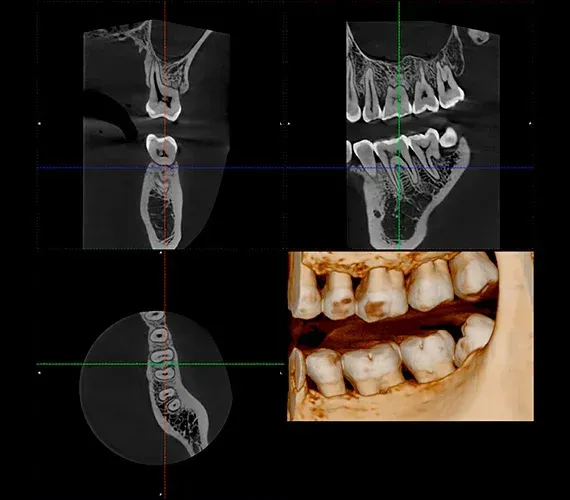

TC Cone Beam

Con questa apparecchiatura vengono eseguiti gli esami 3D delle arcate dentarie.